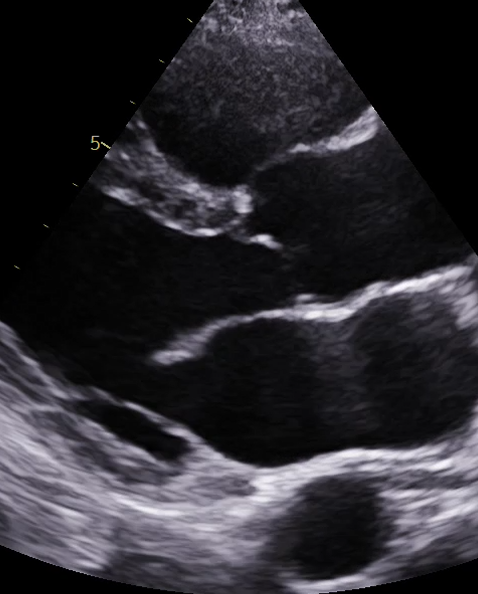

Echocardiogram

– We provide Echocardiogram’s directly to private patients with a GP referral.

– We provide Hospitals and clinics with Cardiac Physiologists to perform Echocardiogram reports